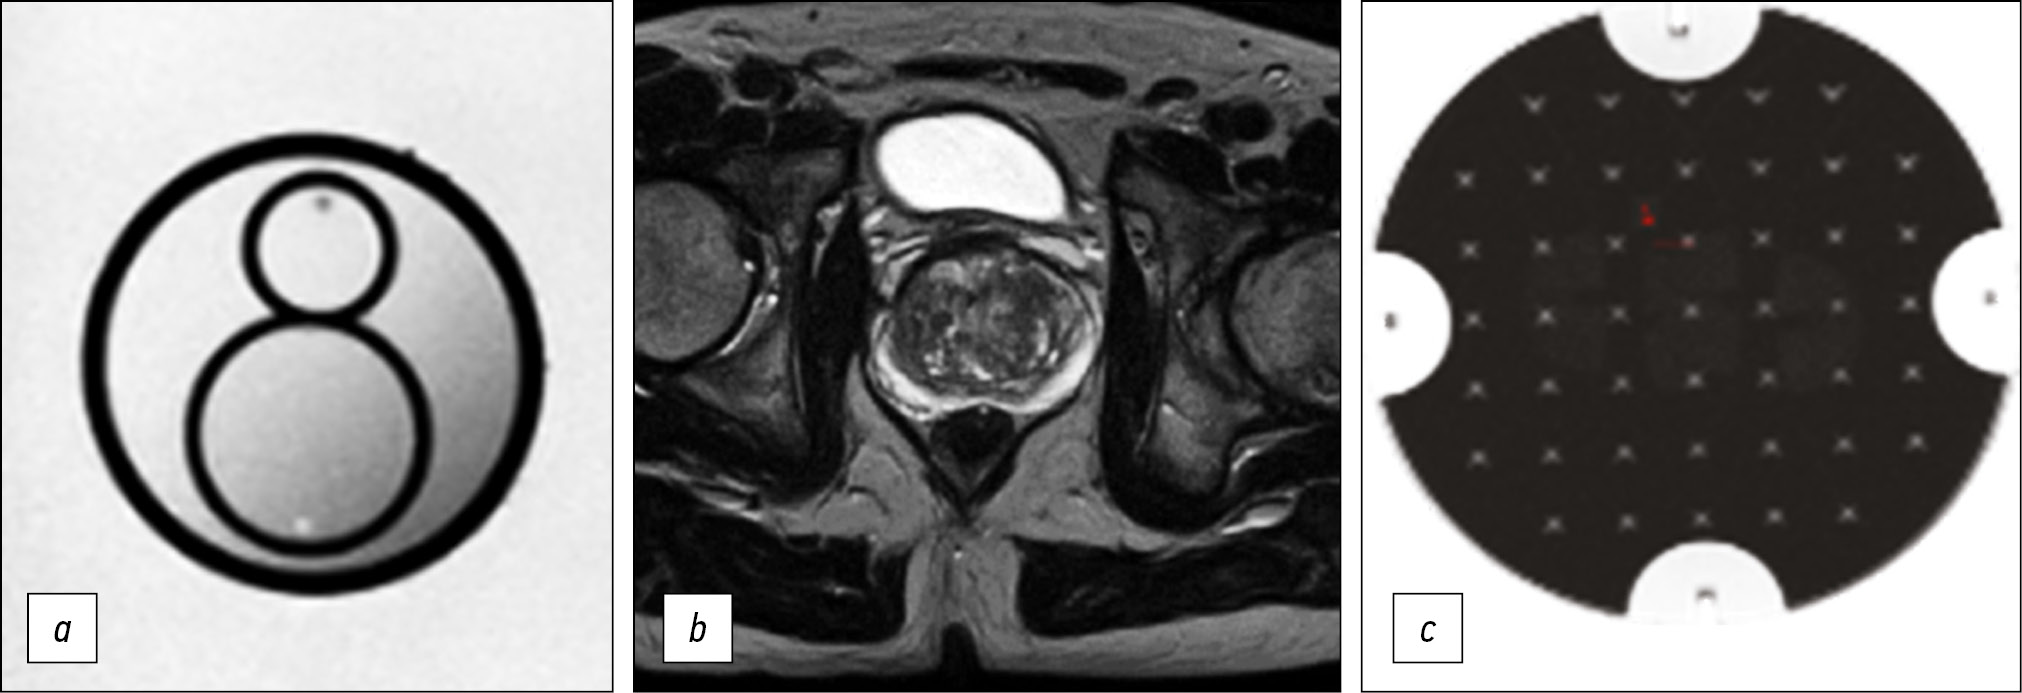

MATERIALS AND METHODS: Preliminary analysis of prostate magnetic resonance imaging scanning in medical organizations of the Moscow Health Care Department showed the absence of a unified approach. Using the iterative adjustment of scanning parameters, we adjusted the protocol to ensure acceptable quality with maximum available compliance with PI-RADS v2.1.

To quantify the quality of the images, we used the magnetic resonance imaging phantom recommended by the American College of Radiology.

RESULTS: The biparametric protocol was developed for Excelart Vantage 1.5 T, including T2-weighted images in three planes and diffusion-weighted images, which took less than 11 min. Moreover, the image quality parameters (intensity inhomogeneity, nonlinearity, resolution, and slice thickness) were within the acceptable ranges recommended by the magnetic resonance imaging manufacturer.